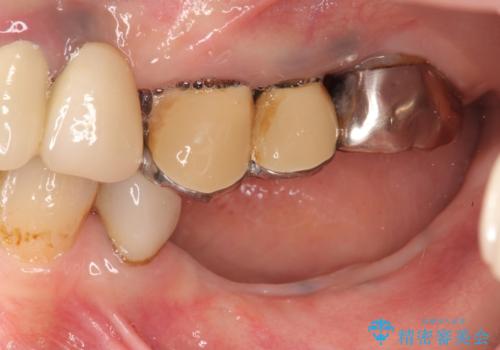

- 左下に長年使用した入れ歯が合わず、よりしっかりと噛みたいという希望で来院されました。

入れ歯をはずししっかりと噛む手段としてインプラント治療を進めていきます。

- 90万円(ストローマンインプラント×2・チタンカスタムアバットメント×2・ジルコニアクラウン×3)費用は治療当時の料金となります

インプラントを用いることで、たくさん失ってしまった奥歯を入れ歯よりもしっかりと噛む状態へと回復することができます。